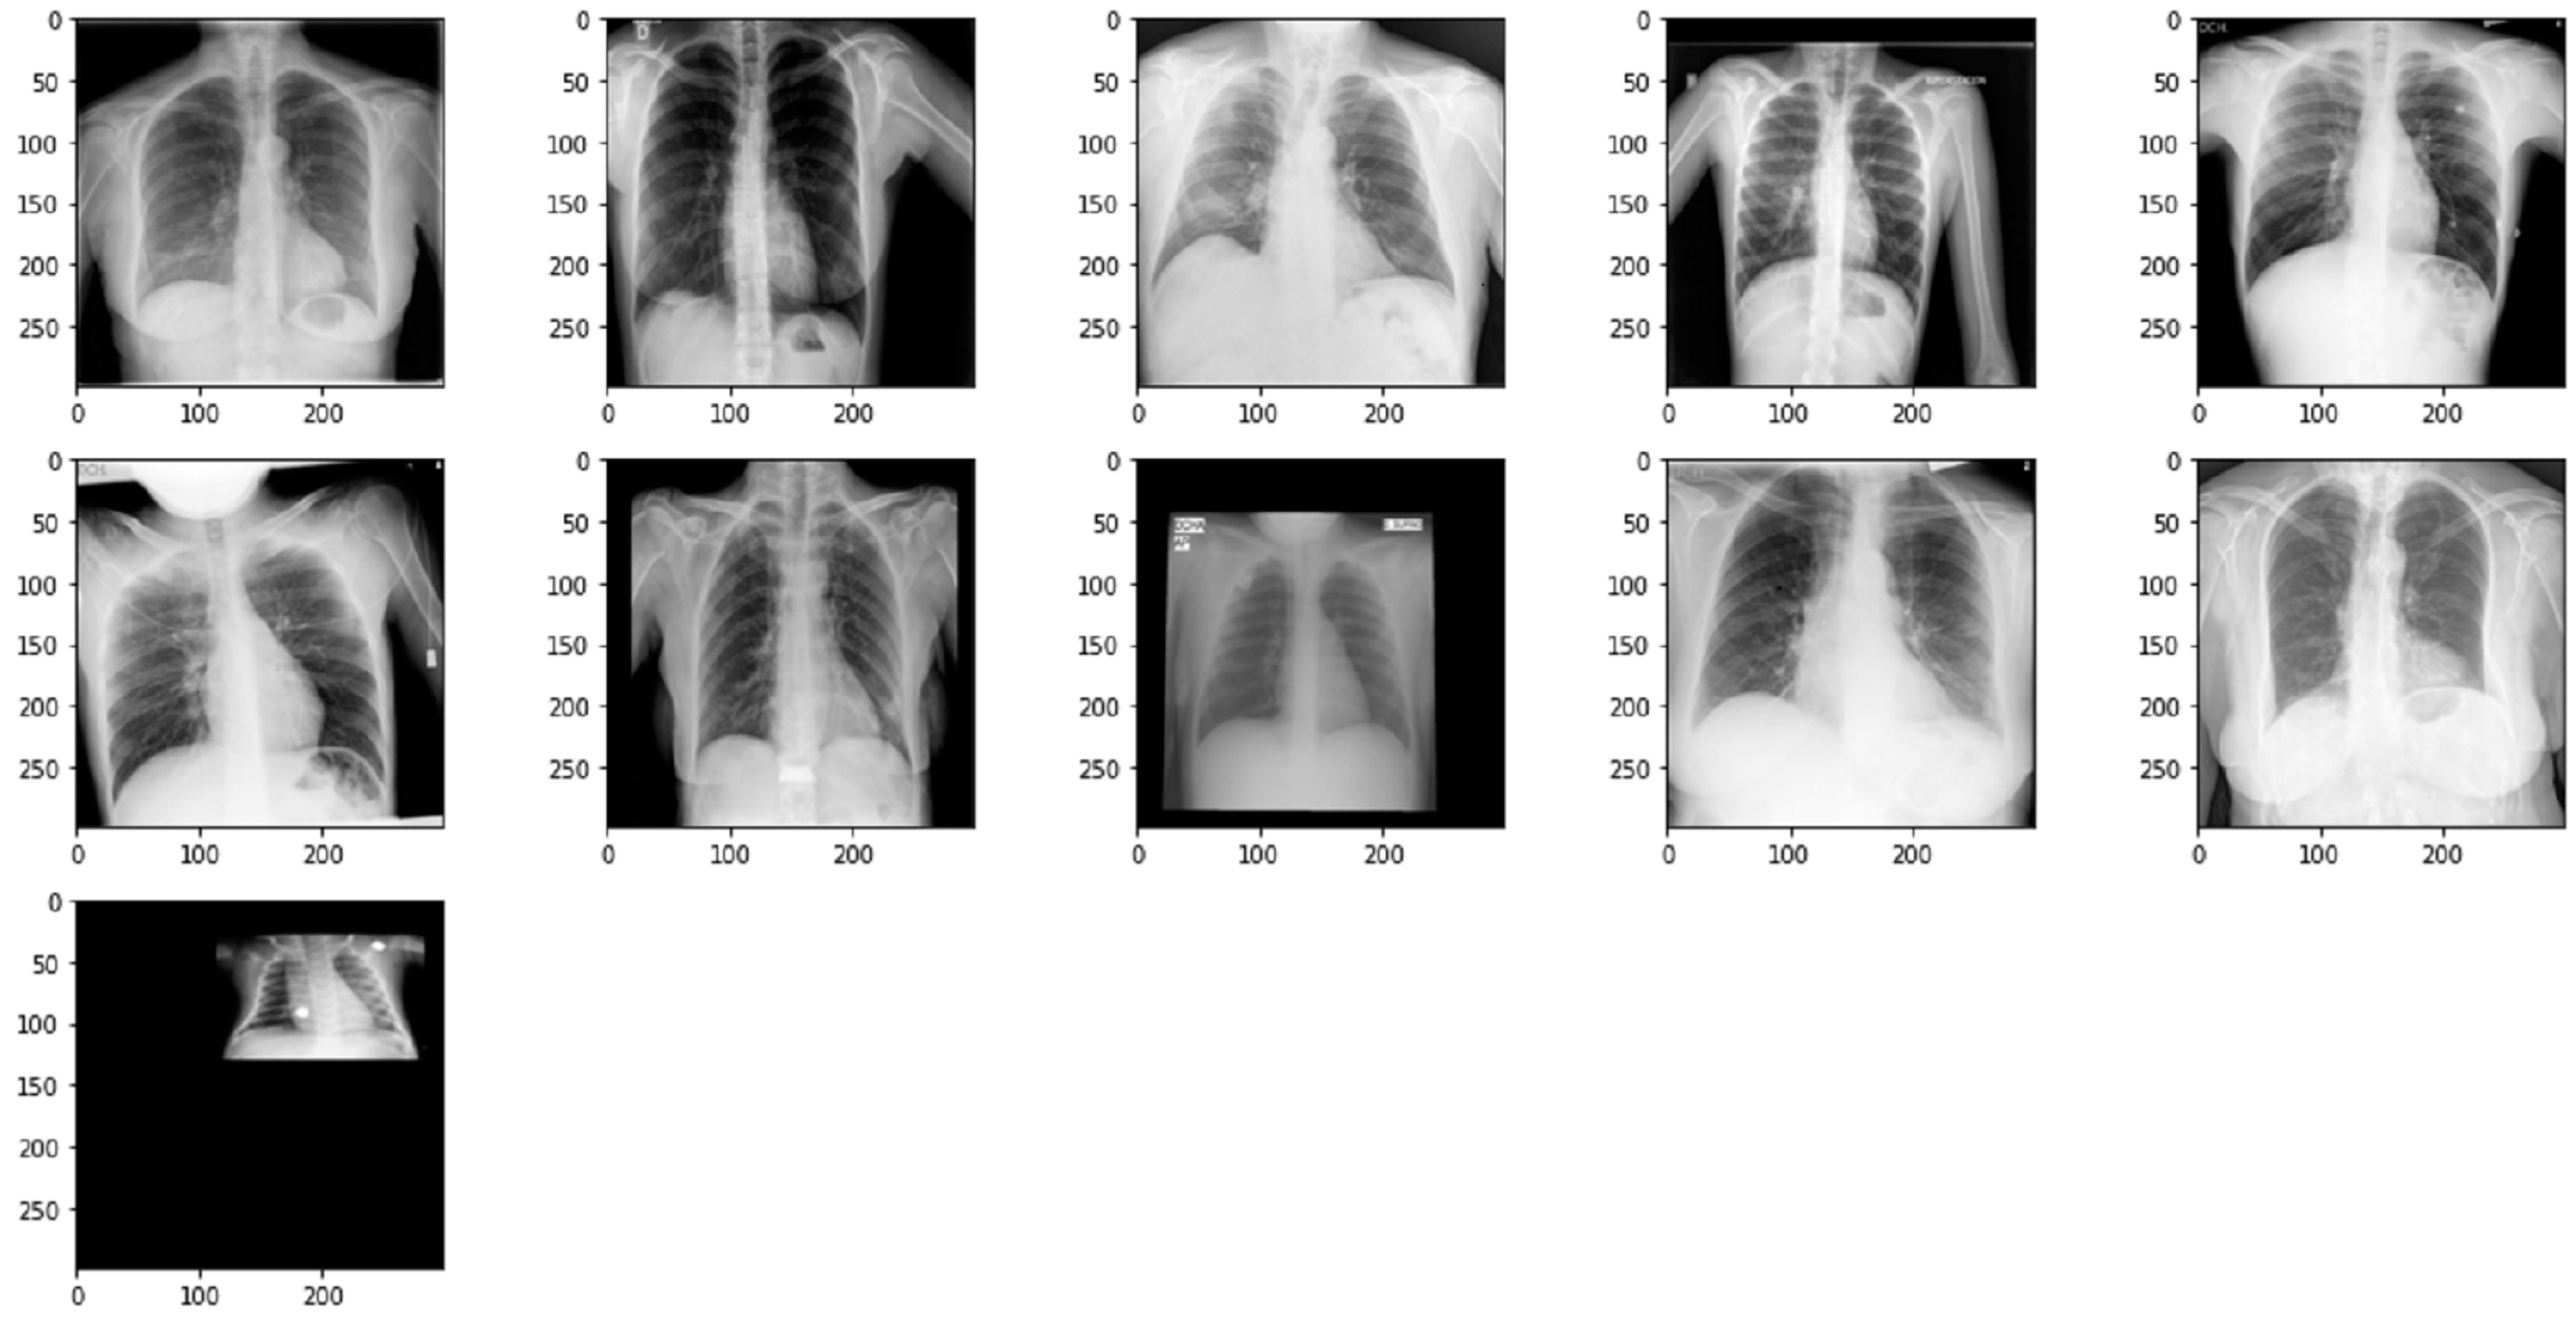

4.3. Evaluation

An evaluation was conducted to assess the performance of the optimal model. The model was validated using a dataset of 1514 observations, including 361 for the COVID-19 class, 1019 for the normal class, and 134 for the pneumonia class. The classification results are presented in Table 9, demonstrating that the model performs well in accurately classifying X-ray images, with a significant number of correct classifications. Out of the total 1514 images, 1497 were classified correctly, resulting in an overall accuracy of 98.88% (1497/1514). However, some errors were observed in the COVID-19 class, with 11 images misclassified as normal. Figure 14 displays the misclassified images for the COVID-19 class, highlighting that some of these images do not meet the required standards, such as being too small, leading to their misclassification.

Figure 14.

Image of COVID-19 misclassified as normal.